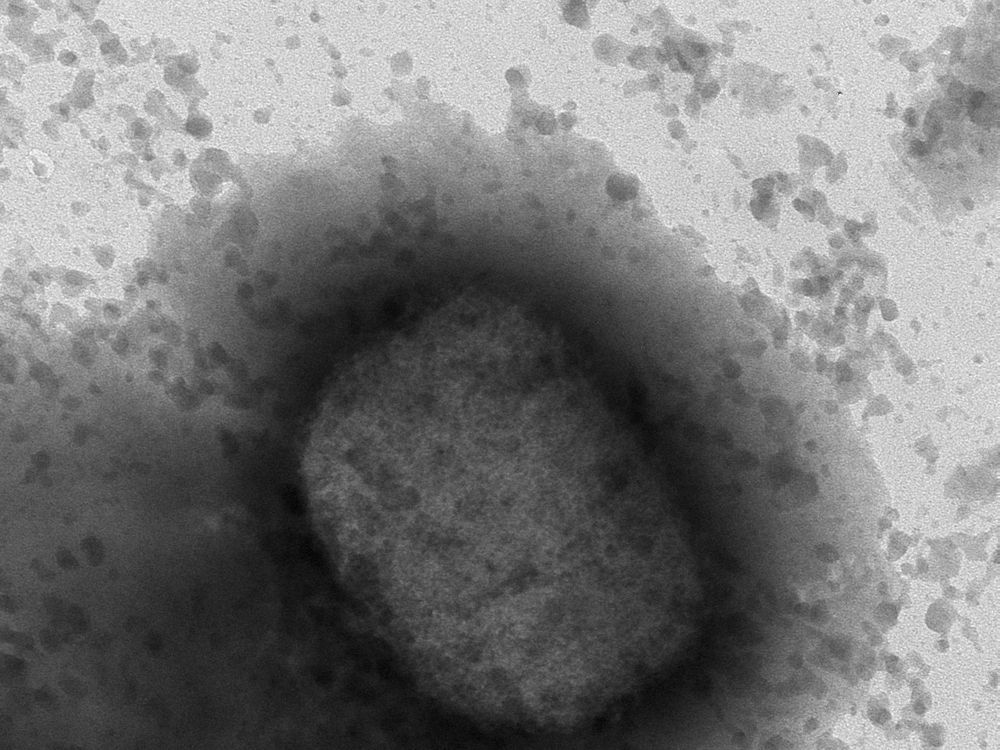

Monkeypox Cases By Area Uk . the uk health security agency (ukhsa) has detected 16 additional cases of monkeypox in england. the uk health security agency says there are currently 287 confirmed cases of monkeypox in england, 10 in scotland,. The number of confirmed monkeypox cases in the uk has risen to 57, with an additional 36 cases reported in. the uk health security agency (ukhsa) is urging people at risk of mpox to get vaccinated, following a rise in. mpox (previously known as monkeypox) is a rare infection most commonly found in parts of west, central. two more people with monkeypox have been identified, taking the total number of cases in the uk to nine. health secretary sajid javid has said another 11 cases of monkeypox have been confirmed in the uk.